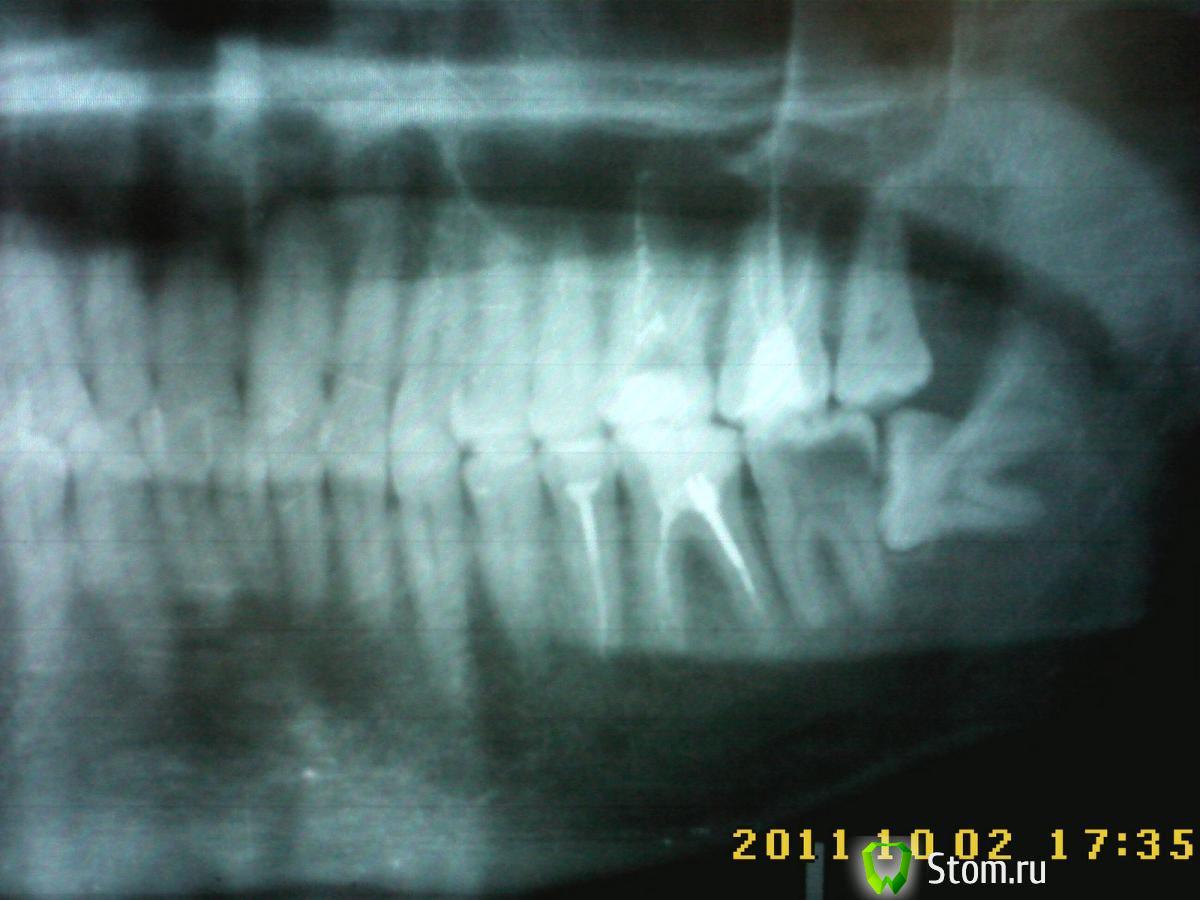

DmitrySH Опубликовано 29 января, 2012 Поделиться Опубликовано 29 января, 2012 У вас на снимке на седьмом зубе обширная кариозная полость через которую происходит инфицирование нерва седьмого зуба. + с восьмым зубом нужно расстаться Ссылка на комментарий

ger_berra Опубликовано 30 января, 2012 Поделиться Опубликовано 30 января, 2012 Причинный зуб у Вас нижний левый 7-й.Пульпитные боли от нижних зубов могут иррадиировать (распространяться) на зубы верхней челюсти,в висок,в голову,в соседние зубы.В 6-ке рядом с ним надо перелечить каналы.Там воспаление на верхушке корня,тоже может периодически обостряться.Зуб мудрости здесь же удалять без промедлений.Из-за него испортился 7-й. Ссылка на комментарий

DmitrySH Опубликовано 30 января, 2012 Поделиться Опубликовано 30 января, 2012 По снимкам - с леченим 7 нижнего зуба особых проблем не должно быть. Я бы разделил работу на 3 этапа. 1. Удаление пораженных кариесом тканей 7 зуба, обработка и пломбирование каналов. Закрытие временной пломбой. После этого будет более удобный доступ к 8 зубу.2. Удаление восьмого зуба3. Востановление седьмого зуба Ссылка на комментарий

kasoleil Опубликовано 3 февраля, 2012 Поделиться Опубликовано 3 февраля, 2012 Сколько у меня есть времени на имплантацию 7 зуба до расползания остальных в сторону удаленного?Может есть смысл сразу при удалении имплантировать чтобы 2 раза не пилить? чтобы понять, насколько это возможно, нужна компьютерная томограмма - посмотреть, как по отношению друг ко другу расположены зубы 3.7 и 3.8, и достаточно ли будет после удаления кости для установки имплантата. по ортопантомограмме принять такое решение не всегда можно Ссылка на комментарий